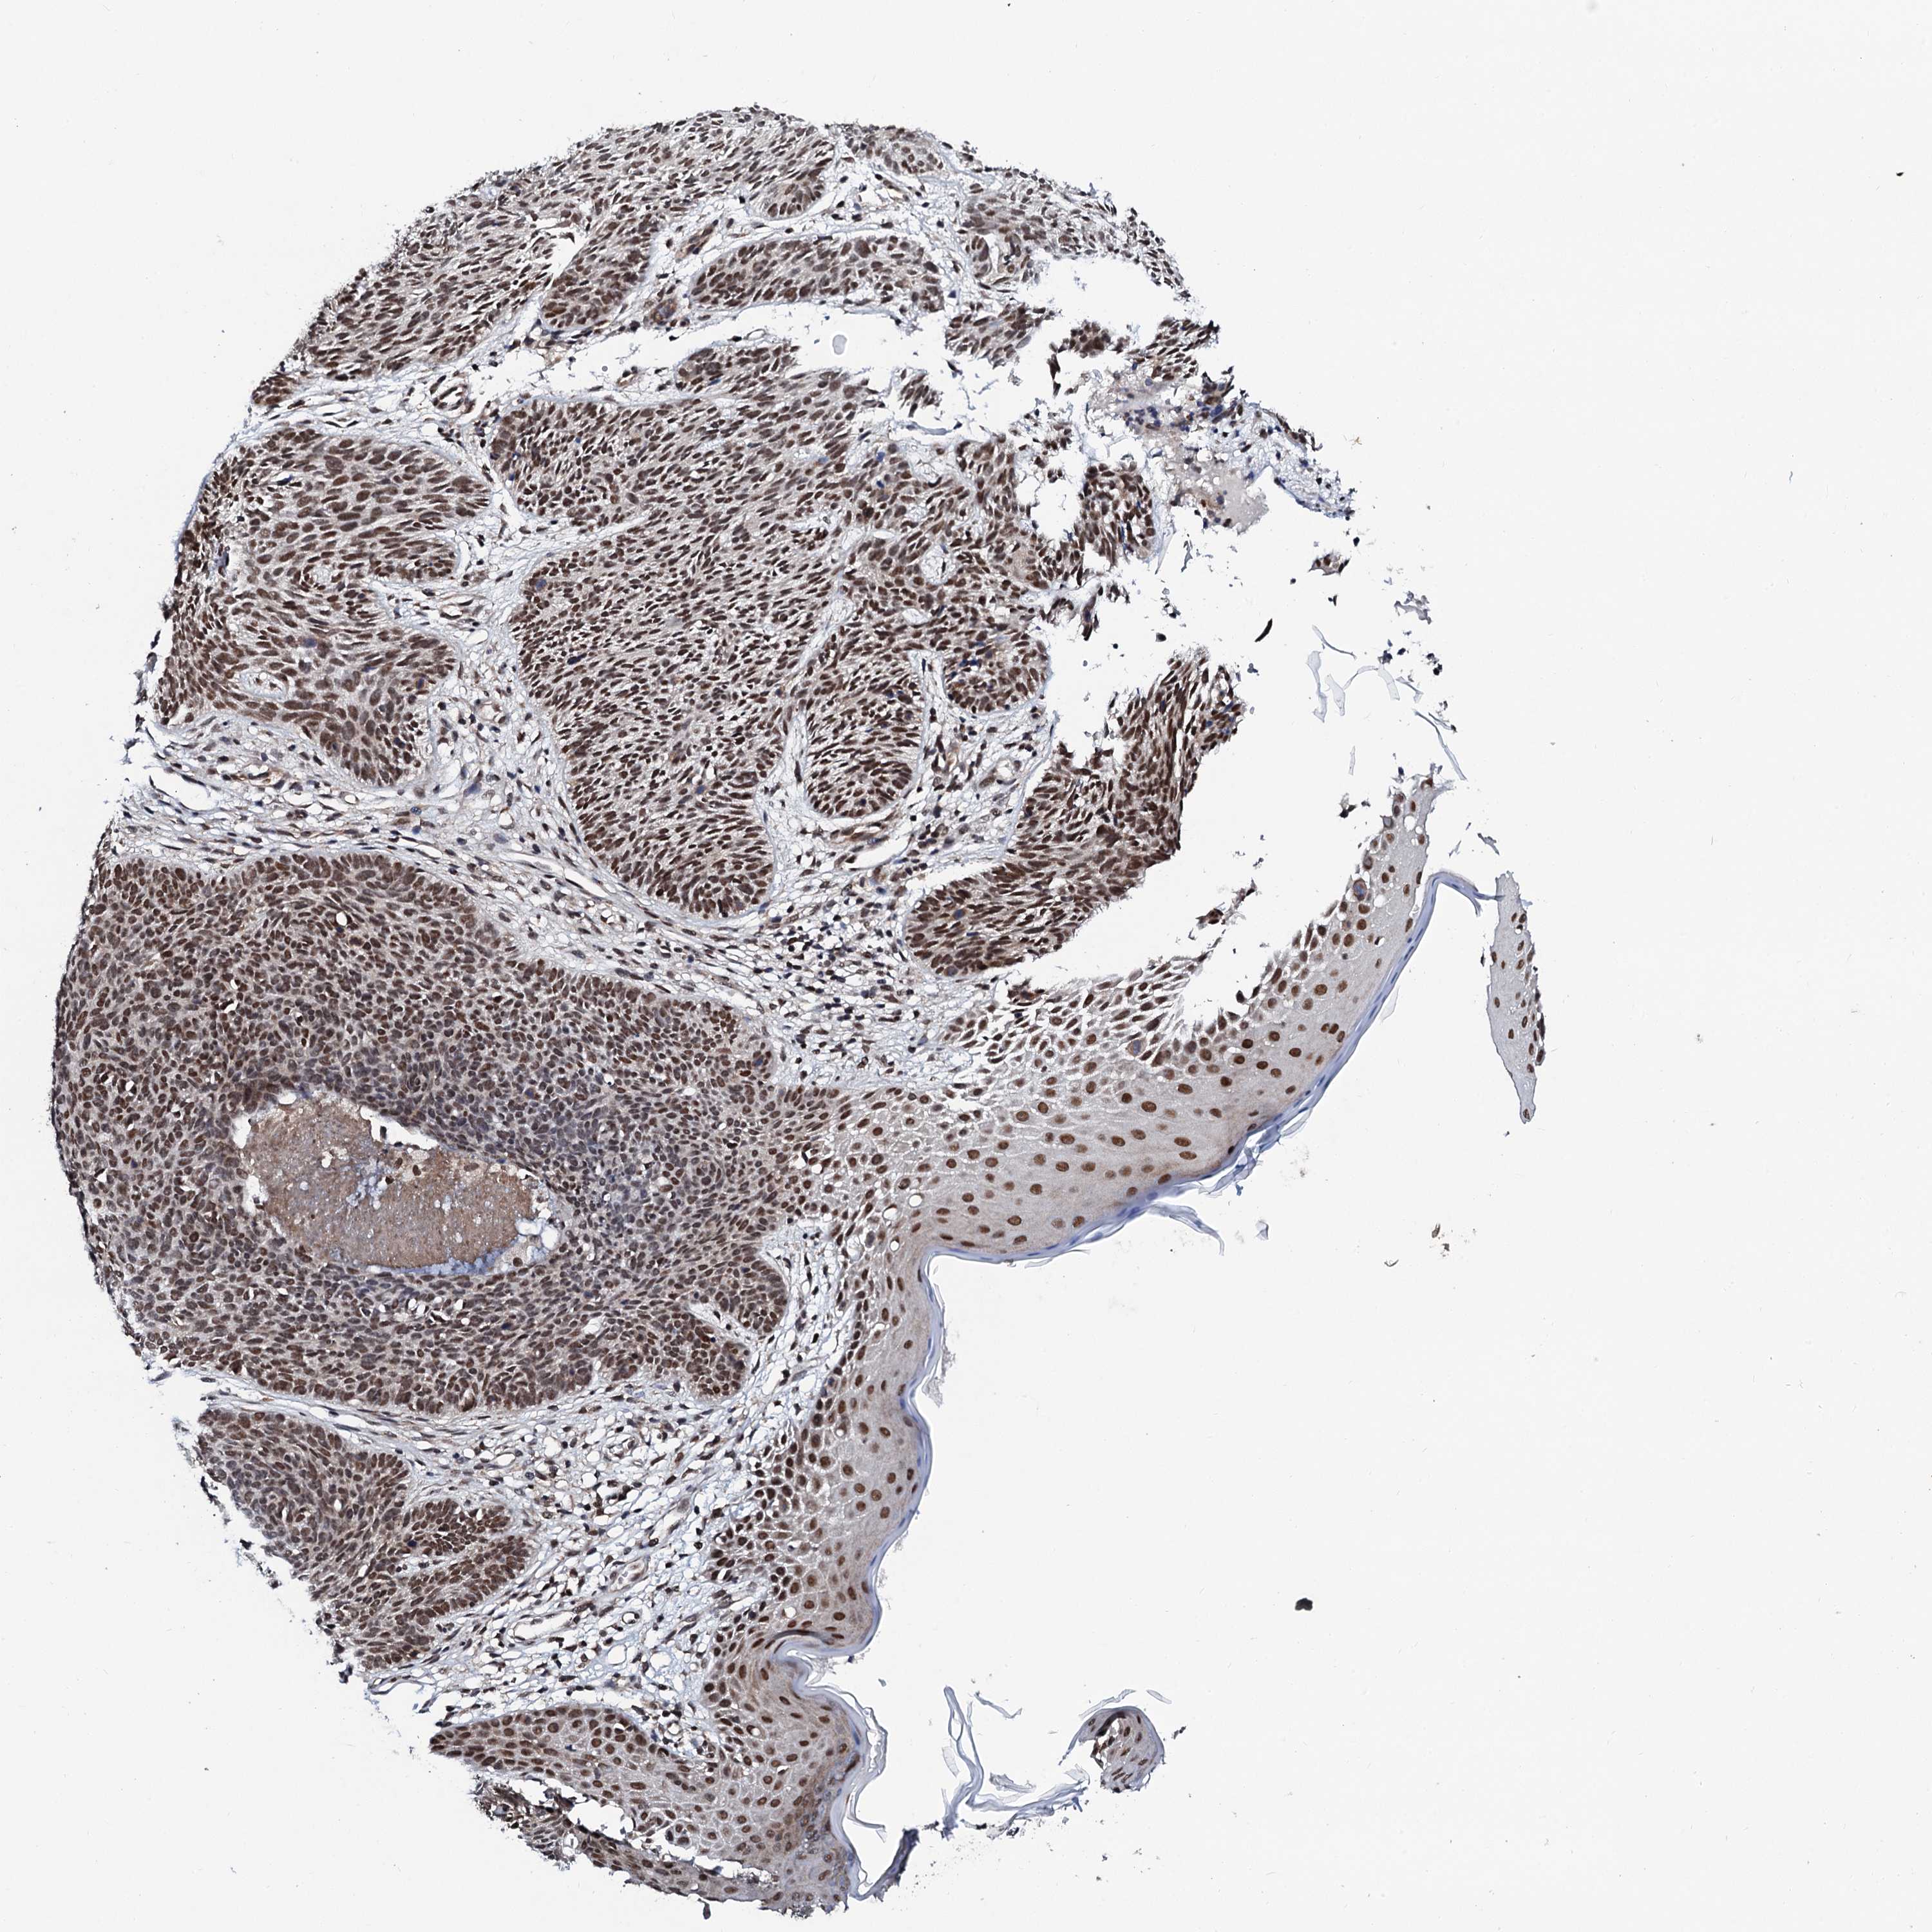

SKIN CANCER - Protein expressioni

A mouse-over function shows sample information and annotation data. Click on an image to view it in a full screen mode. Samples can be filtered based on level of antibody staining by selecting one or several of the following categories: high, medium, low and not detected. The assay and annotation is described here.

Antibody staining in the annotated cell types in the current human tissue is reported as not detected, low, medium, or high, based on conventional immunohistochemistry profiling in selected tissues. This score is based on the combination of the staining intensity and fraction of stained cells.

Each image is clickable and will lead to virtual microscopy that enables deeper exploration of all samples and also displays staining intensity scores, fraction scores and subcellular localization as well as patient and tissue information for each sample.

Antibody HPA039743

Staining

High

Intensity

Strong

Quantity

>75%

Location

Nuclear

Basal cell carcinoma